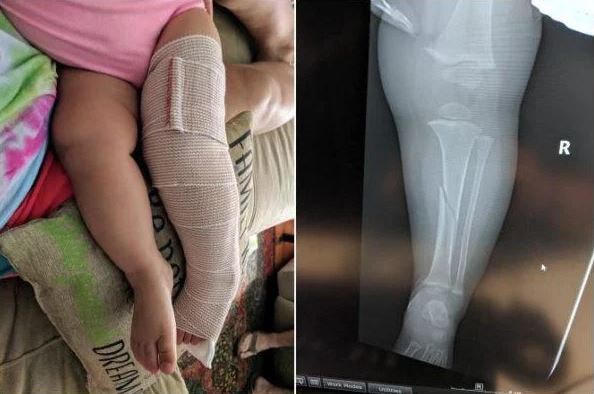

Chơi cầu trượt cùng bố, bé gái 4 tuổi bị gãy xương chày đầu gối

Thêm một trường hợp trẻ bị gãy chân khi chơi cầu trượt cùng bố mẹ. Bé Emelyn, ban đầu cười rất thích thú khi được bố bế vào lòng để chơi cầu trượt, nhưng khi trượt xuống đến nơi bé bỗng khóc không ngừng do chân bị kẹp giữa thành cầu trượt và chân của bố mình. Tai nạn này đã khiến xương đầu gối của bé bị xoắn gãy và phải bó bột trong suốt 4 tuần liền. Đối với cha mẹ bé, anh Matthew và cô Kayla, đây là sự việc quá đỗi đáng sợ và họ sẽ không bao giờ quên được.